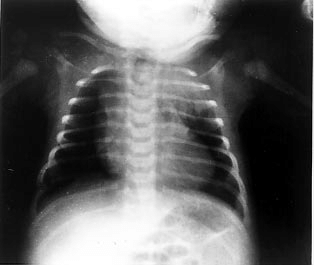

Hipofluxo pulmonar ûˋ a diminuiûÏûÈo do fluxo sanguûÙneo nas artûˋrias pulmonares, ou seja, menos sangue chega aos pulmûçes para ser oxigenado.

Na radiografia, os principais sinais sûÈo:

- ô Vasos centrais pouco calibrosos;

- ô Vasos perifûˋricos de calibre reduzido;

- ô Sinais de aumento do VD;